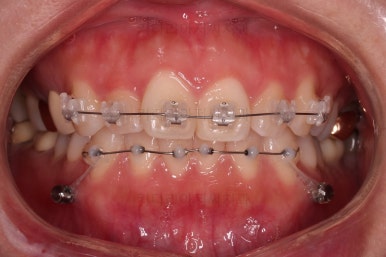

이번에 부산부분치아교정 환자분이 선택하신 장치는 엠파워 클리어라고 하는 자가결찰 세라믹인데요.

흔히들 아시는 클리피씨가 이러한 종류의 장치에요.

아랫니는 일반 브라켓 보다 매우 작은 장치가 들어갔는데요.

미니튜브 장치에요.

장치 부착 직후의 얼굴 모습인데요.

입이 얼마나 나오는지에, 웃을 때 보이는 브라켓의 모습은 어떤지 참고해 주세요.

이번 환자분은 브라켓을 부착했다고 해서 입이 거의 나오지 않는 경우였어요.

이처럼 입이 얼마나 나올지는 사람마다 매우 달라서 일단 붙여봐야 아는 경우가 많답니다.